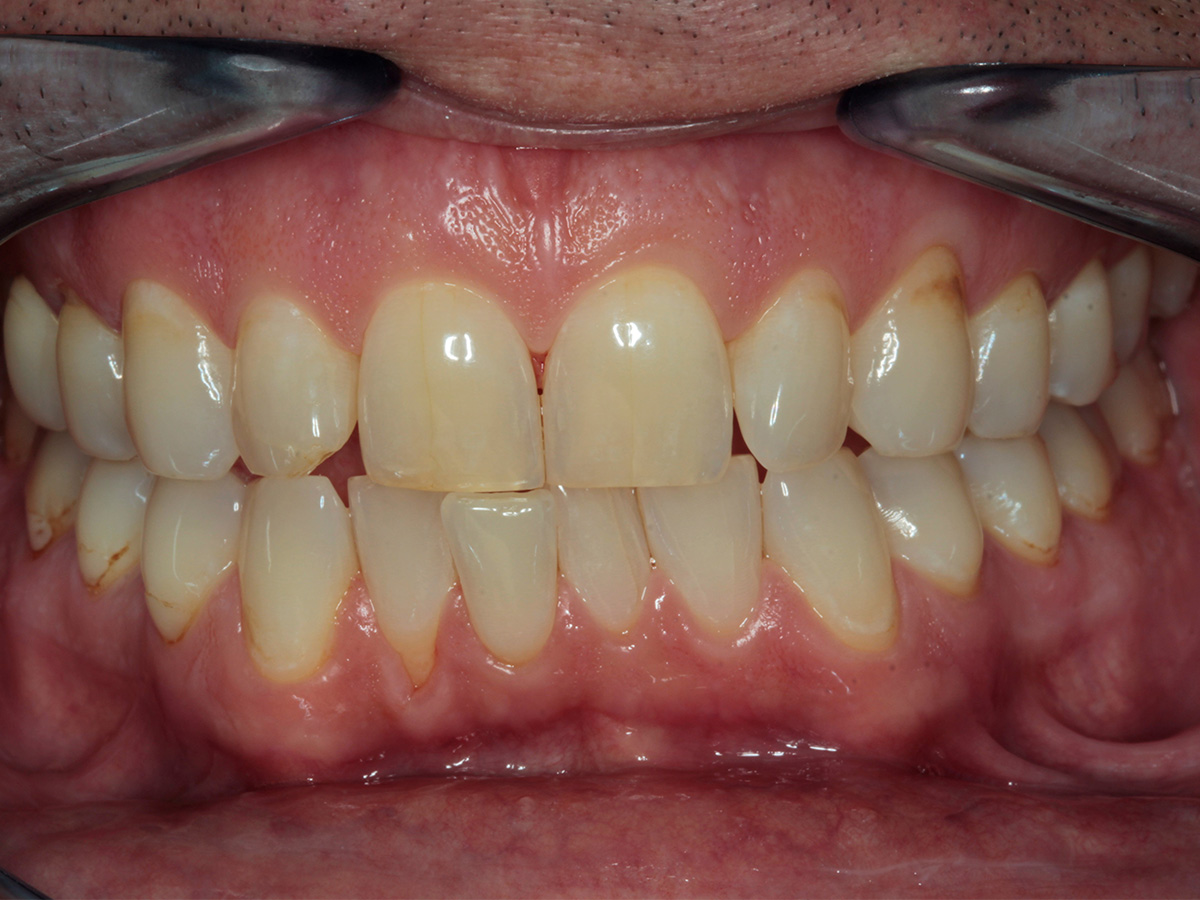

In diesem Workshop erhalten Sie umfassendes Wissen für die Behandlung von Parodontitis-Patientenen. Zunächst führt Sie Yvonne Gebhardt durch moderne subgingivale Behandlungskonzepte – das Herzstück der PA-Therapie. Anschließend erklärt Ihnen Sonja Steinert die faszinierenden Zusammenhänge des Knochenstoffwechsels: Wie Entzündungen den Knochenabbau fördern und wie Sie mit gezielter Therapie und Vitamin D gegensteuern können.

• Parodontale Krankheitsbilder erkennen